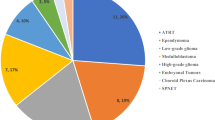

Meningiomas are histologically classified according to the WHO grading system. The most recent revision of the WHO grading system was published in 2007, with the most significant change recognizing brain invasion as reflecting more aggressive biological potential. Most pediatric meningiomas are WHO grade I (80.6%) with WHO grade II (10.4%) and III (8.1%) tumors occurring less frequently (Figs. 1, 2 and 3) [38].

In adults, the incidence of WHO grade II and III meningiomas is lower than in children, constituting 4.7–7.2% and 1.0–2.8% of cases, respectively [39]. Metastatic meningioma is extremely rare in children, with isolated cases of extracranial metastases reported in the lung, liver, lymph nodes, and bone in patients with WHO grade III meningiomas [26, 40–42]. Similarly, metastatic disease is rare in adults, estimated to occur in 0.1% of patients [43]. There is a known association between clinical behavior and histological grade. The association is stronger for sporadic adult meningiomas, because one study has shown recurrence/death to be relatively common in pediatric patients with WHO grade I tumors [15]. However, recurrence-free survival was significantly related to WHO grade in the largest published cohort of pediatric meningiomas [9]. Atypical and malignant transformation is a recognized phenomenon and has been identified in several cases at recurrence [44].